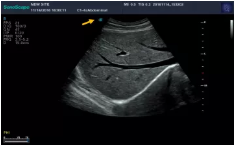

Mark點:每一把探頭都有一個mark點,是用于定位方向, mark點一側(cè)始終對應著圖像S點(圖像箭頭標識)一側(cè)。

左室長軸